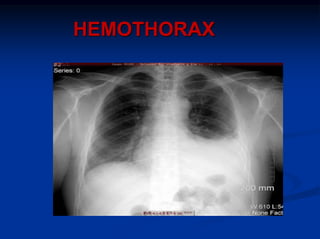

HEMOTHORAX

Blunt or penetrating trauma

Bleeding from; lung laceration, intercostal

vessel, internal mammary artery, T-spine #

Usually self-limiting

if large enough to appear on CXR needs ICC

ICC reduces late incidence of empyema or

fibrothorax.